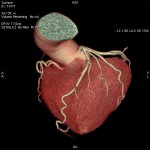

CT検査

当院では各診療科からの検査依頼があり、診断用CTが2台、放射線治療計画用CTが1台稼動しています。

CTの原理を簡単に説明します。

CTの寝台に寝ていただき、その寝台が動きながら検査を行います。寝台がガントリー(X線発生器と検出器等から構成)と呼ばれるドーナツ状の機械を通過する際に、X線を照射し、検出しています。物質のX線の吸収差を利用して、360度方向からのデータを再構成することで輪切りの画像が完成します。空気や水などX線を吸収しにくいものは黒く、骨などX線を吸収しやすいものは白く表示されます。

また、造影剤を静脈から注射することで区別が難しかった目的の臓器や病変も見やすくなります。しかし副作用のリスクがあるためヨード過敏症の方や過去に副作用が出現した方、腎臓の機能が悪い方は主治医にお申し出ください。

当院のCT装置の最薄スライス厚は0.625mmで、これにより一つの断面だけでなくいろいろな角度からの断面を構築することや、血管や骨の3次元表示を可能にしています。また、2021年2月に導入された装置では、2種類のエネルギーを使用して撮影することで、コントラストの増強、アーチファクトの低減、さらに特定の物質を強調したり抑制した画像が作成でき、診断能の向上が見込めます。

CTについてわからない点や不安なことがありましたら担当の技師または看護師にご相談ください。